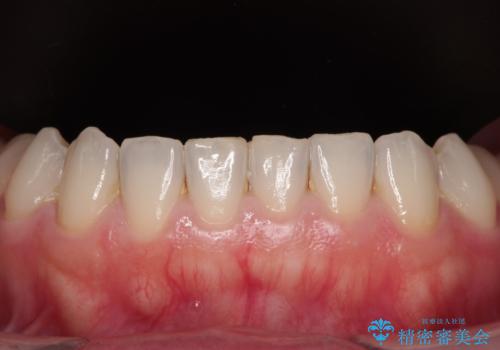

- 奥歯の銀歯をセラミックにしたいとのことで来院された患者様です。

当初は奥歯のみの治療をご希望でしたが、話を進めていくうちに、軽度ではあるものの、幼少期の薬の影響で歯が変色していることがコンプレックスであるということが分かりました。

長年歯の色が塞ぎ込んでいた部分があるとのことで、これを機会に全ての歯を真っ白にするために、オールセラミッククラウンにて補綴治療を行うこととしました。

より白さが目立つように、自然な仕上がりではなく、作り物の雰囲気があるフルジルコニアクラウンにて補綴治療を行いました。